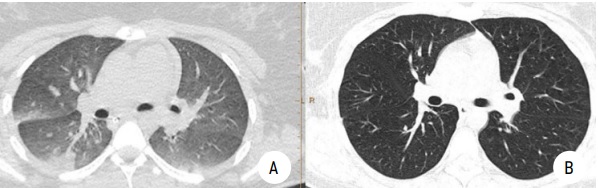

Рисунок 2.

МСКТ легких с контрастированием. Пациентка 2:

А — субмассивная ТЭЛА, правосторонняя полисегментарная инфарктная пневмония;

B — контрольная МСКТ с контрастированием через 30 дней после начала лечения. Выраженная положительная динамика

Figure 2.

MSCT of the lungs. Patient 2:

A — submassive pulmonary embolism, right-sided polysegmental infarct pneumonia;

B — control MSCT 30 days after the start of treatment. Significant improvement.

В отделении была продолжена терапия варфарином, для достижения целевого значения МНО (2–2,5). При МСКТ органов грудной клетки с контрастированием через 1 месяц от начала терапии отмечена положительная динамика в виде полного регресса тромбоэмболии и очагов инфаркт-пневмонии (рис. 1, 2). В настоящее время пациентка проходит обследование у гематолога.